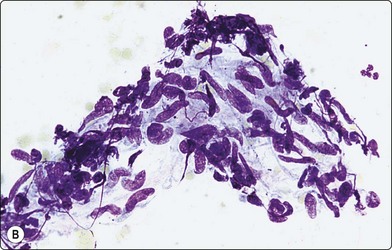

In Southeast Asia and China, Penicillium marneffei, a rapidly emerging opportunistic infection in HIV-positive patients, has 2–4-micron yeasts in macrophages and sausage shaped yeasts in the extracellular background, showing septa in the GMS due to their division by binary fission, not budding.49,50 The budding yeasts of Sporothrix schenkii are cigar shaped (Fig. 18.10),51,52 and Paracoccidioides brasiliensis, endemic in Central and South America, has variably sized yeasts with pathognomonic multiple budding.33,53

image image image

Fig. 18.10 (A, B, C) Sporotrichosis: oval and elongate yeasts in macrophages and in the GMS in the background (Pap, Giemsa, Grocott Methenamine silver, ×1000).